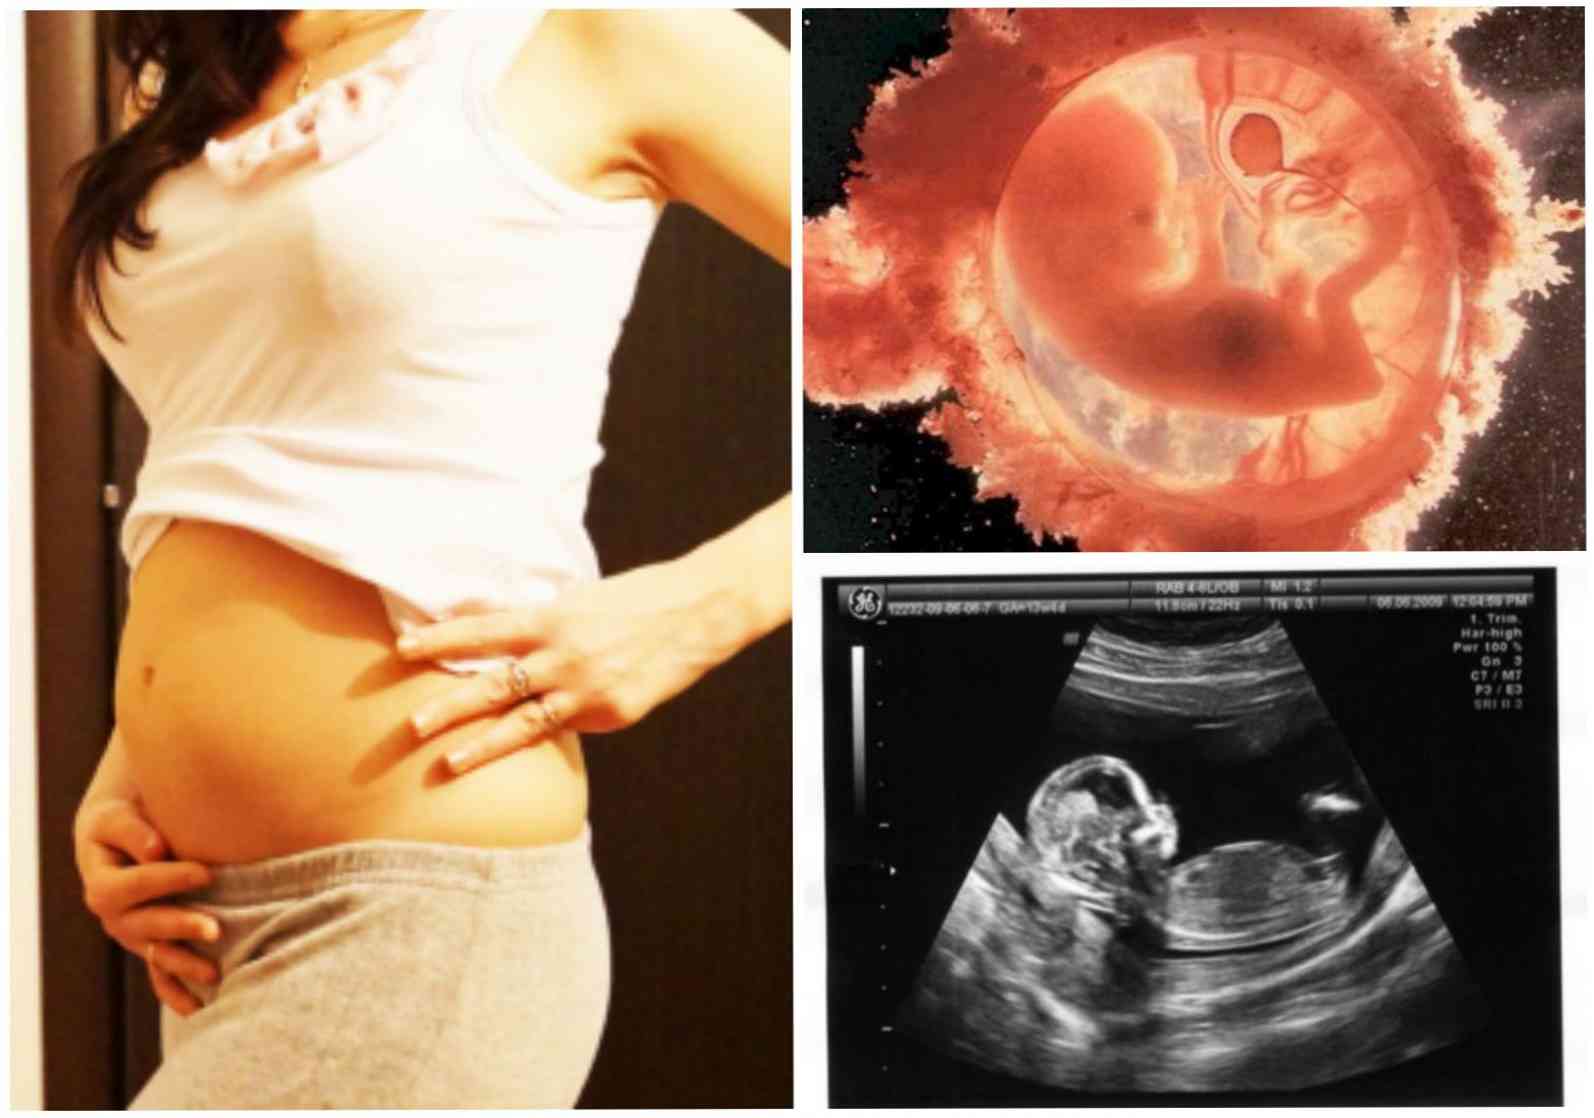

Ваш ребенок имеет длину 74мм, вес 30 гр.